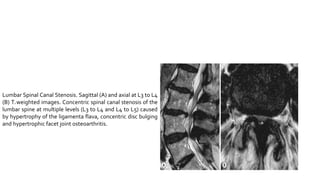

Lumbar Spinal Canal Stenosis. Sagittal (A) and axial at L3 to L4

(B) T2 weighted images. Concentric spinal canal stenosis of the

lumbar spine at multiple levels (L3 to L4 and L4 to L5) caused

by hypertrophy of the ligamenta flava, concentric disc bulging

and hypertrophic facet joint osteoarthritis.

Lumbar Spinal CanalStenosis. Sagittal (A) and axial at L3 to L4 (B) T2 weighted images. Concentric spinal canal stenosis of the lumbar spine at multiple levels (L3 to L4 and L4 to L5) caused by hypertrophy of the ligamenta flava, concentric disc bulging and hypertrophic facet joint osteoarthritis.